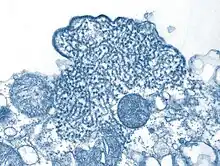

Transmission electron micrograph (TEM) depicted a number of Nipah virus virions from a person's cerebrospinal fluid (CSF).

During acute and convalescent stages of the disease, RNA can be detected using reverse transcriptase polymerase chain reaction (RT-PCR) from throat swabs, cerebrospinal fluid, urine and blood analysis.[1]